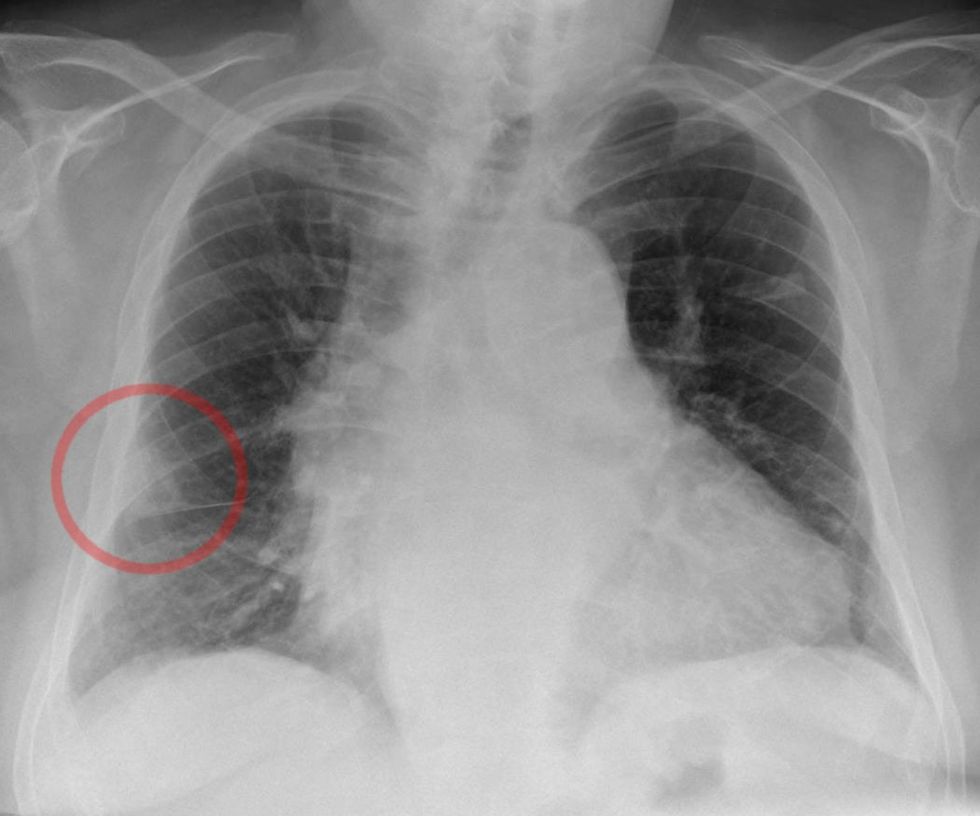

Imazh i mushkërive me rëntgen

Përmes imazhimit me rëntgen diagnostikohen sëmundje dhe anomali të kockave, nyjeve, mushkëri, gjinjve, barkut dhe të dhëmbëve.

Rrezet rëntgen janë rreze të depërtueshme dhe në mjekësi përdoren për imazhimin e pjesëve të trupit. Gjatë kalimit të rrezeve rëntgen nëpër inde të ndryshme të trupit me dendësi të ndryshme (eshtrat, muskujt, organet, mushkëritë, gjinjtë) ato absorbohen në masë të ndryshme nga këto inde dhe si pasojë imazhi i përfituar merr karakteristikat e pjesës së trupit të imazhuar.

Imazhi i përfituar është dy dimenzional (gjatësinë dhe gjerësinë e pjesës së vizualizuar të trupit). Pjesët me dendësi më të madhe paraqiten si hije (rrezet nuk kanë depërtuar nëpër indin ose me depërtim minimal) dhe në imazhin filmik vizualizohen si të bardha, derisa pjesët e indeve të buta vizualizohen si transparencë (rrezet kanë kaluar me absorbim minimal nga indi) në film paraqiten si të errëta.